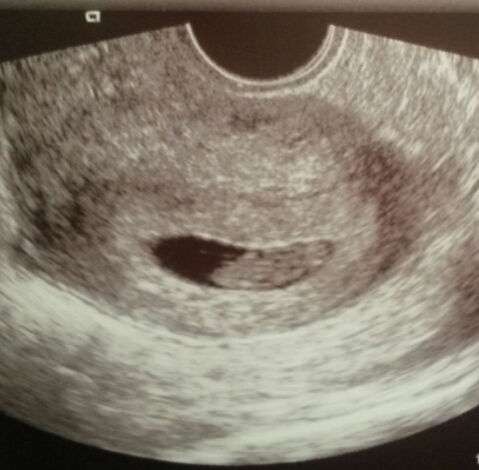

Well the epu couldn't find a reason for the bleed and baby has a strong heartbeat measuring 8 weeks 2 days so I'm happy and just going to try and take it easy Smile

Lovely scan pic newbian all these scans are making me so excited to see mine!

Such lovely scan pics - it's so nice to see them.